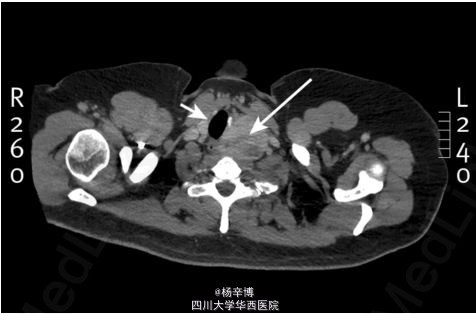

患者体格检查未见异常,常规血液检查、心电图未见异常。 胸片、胸部CT异常 器官明显右偏,上纵隔见均质密度影(箭头) 前纵隔巨大包块,甲状腺来源可能

分析:患者年龄不考虑畸胎瘤,无腺病及B类症状暂不考虑淋巴瘤。CT证实甲状腺包块,血清甲状腺激素未见异常。90%胸骨下甲状腺可位于前纵隔。劳累性呼吸困难在器官狭窄低于8mm可出现。该患者接受了颈入路偏侧甲状腺切除术,术后病理提示多发结节状甲状腺组织,未见恶性细胞。